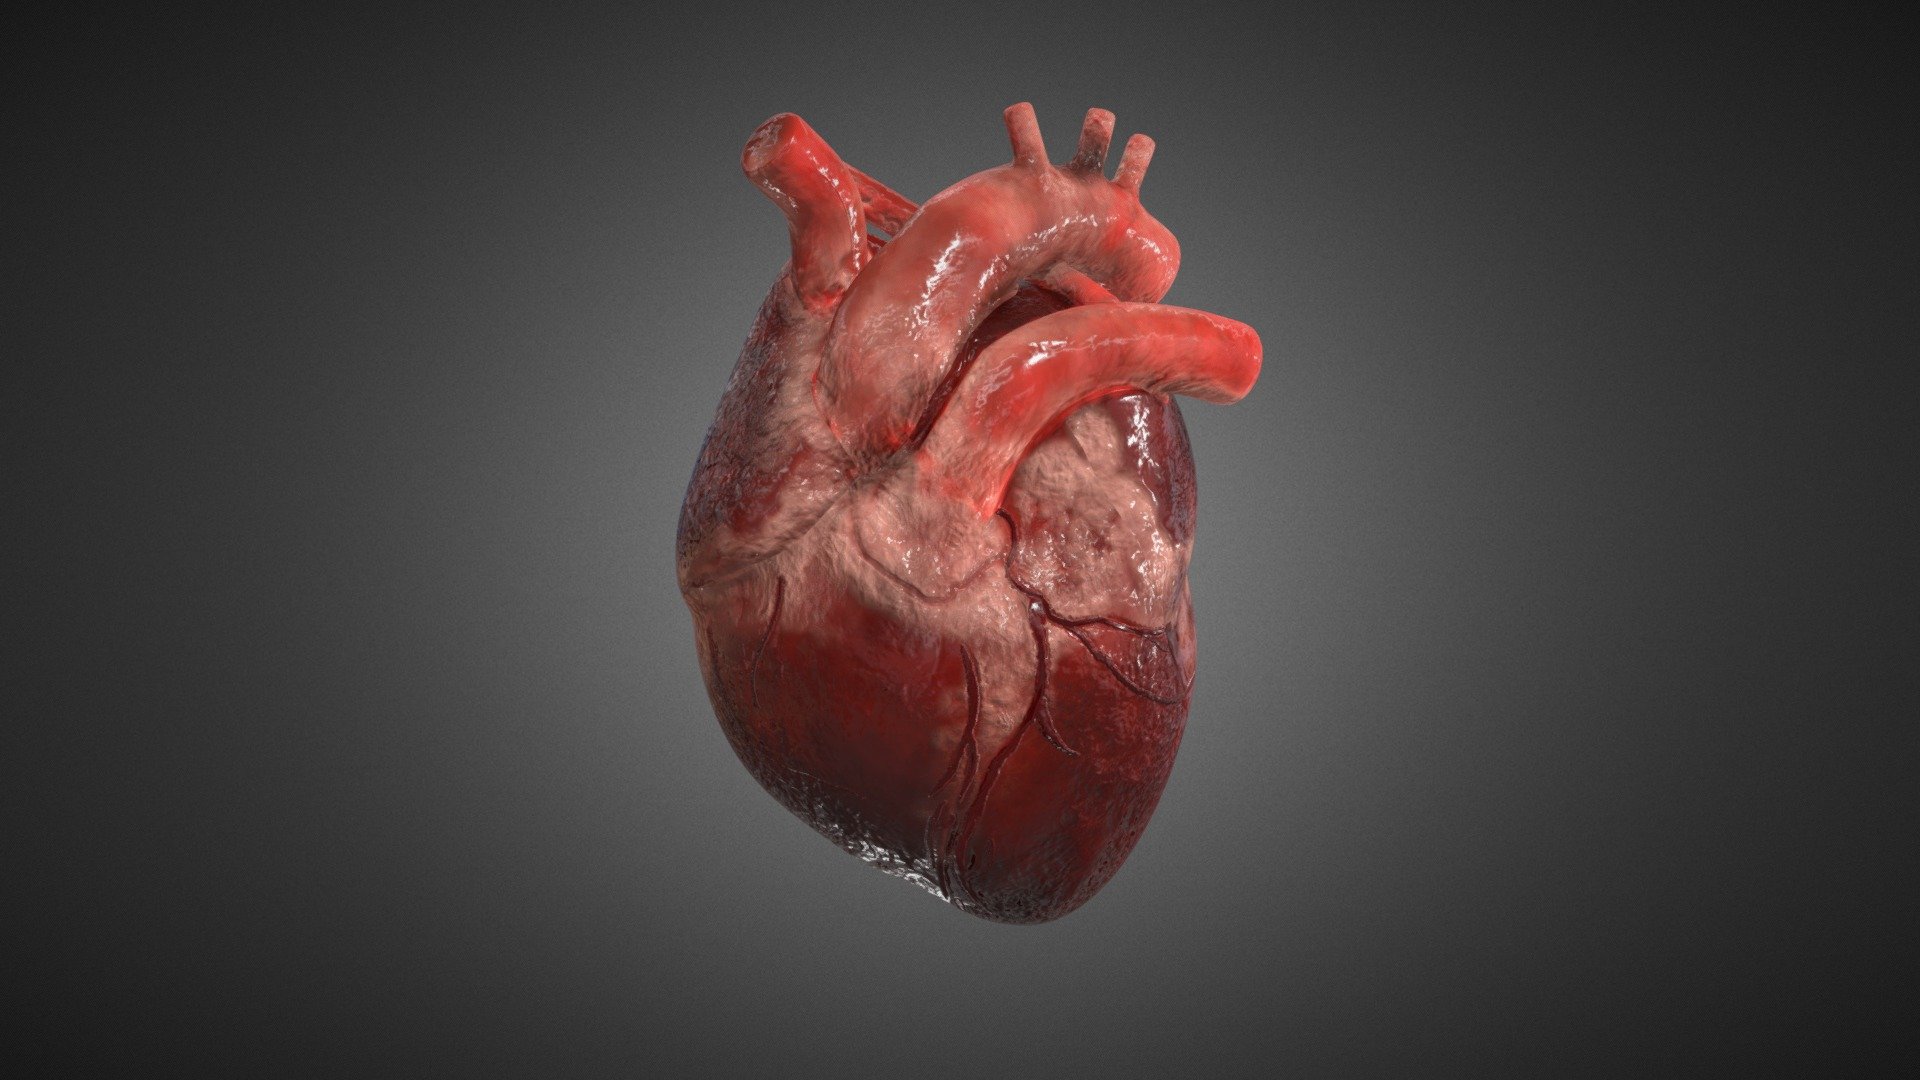

Human Heart Biology